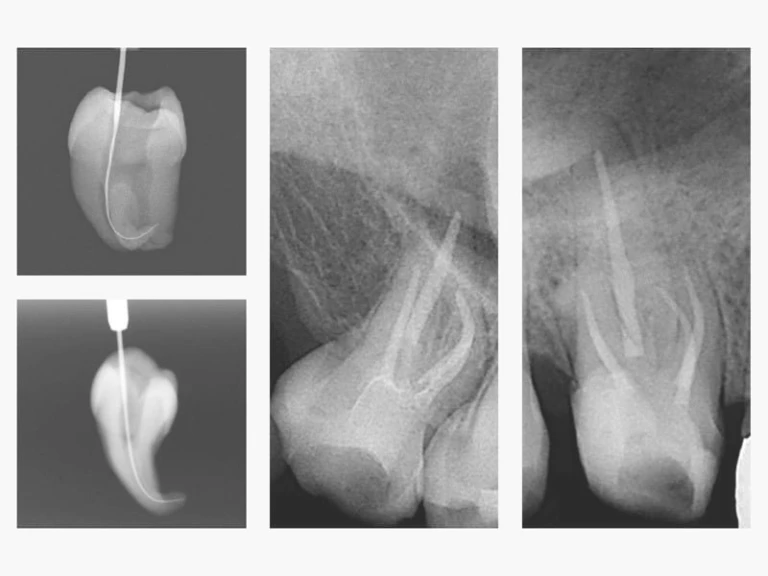

Xử lý khẩn cấp nội nha (phần 1)

Chẩn đoán chính xác và xử lý hiệu quả các cơn đau cấp tính có thể là một trong những…